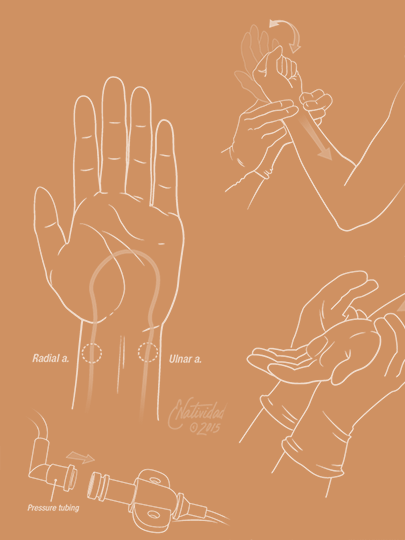

Running series of animated visual abstracts, Quick Takes, created for The New England Journal of Medicine as part of a team of illustrators, medical writers, and scientists. These short, iconographic animations aim to succinctly describe clinical trials and increase the awareness and understanding of important research findings.

Adopting The Journal’s visual style and asset library, I am responsible for the entire production process including narration editing, storyboarding, layout, illustration, and animation.